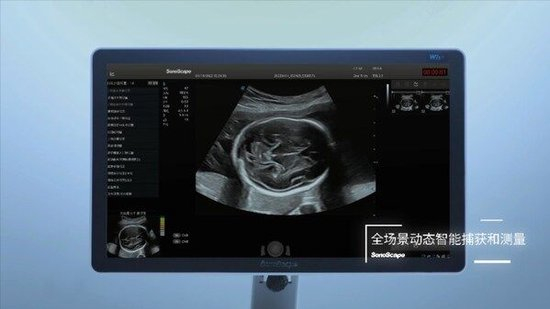

作为国内首个获批的产前超声切面智能辅助识别与测量功能,凤眼™S-Fetus®深度融合了超声技术与人工智能,首个实现"全流程、全场景产筛智能化",让开立超声成为全球首个具备切面自动抓取、测量分析、超声质量控制的"整机智能",将积极推动产前超声智能化转型的进程。

凤眼™S-Fetus®的问世带来了前所未有的变革。作为国内首个基于深度学习的产科超声智能检测技术,凤眼™S-Fetus®也是全球首款基于动态图像对标准切面自动抓取的人工智能技术,能够对超声图像中的组织结构进行实时检测,自动抓取标准切面并进行自动测量,并实现了检查过程中的实时质控,显著提高了产前超声检查的效率和准确性。

凤眼™S-Fetus®支持精确的胎儿生物学测量,并自动发送至报告,使医生的工作流更加顺畅,有效节约了扫查时间,让医生更专注于患者的诊断与治疗。"全流程、全场景产筛智能化"将有力为医生的工作负荷做"减法",同时有助于提升基层医生和年轻医生获取标准切面的能力,推动产前超声技术的智能化、高效化发展,加速超声行业的技术创新进程。